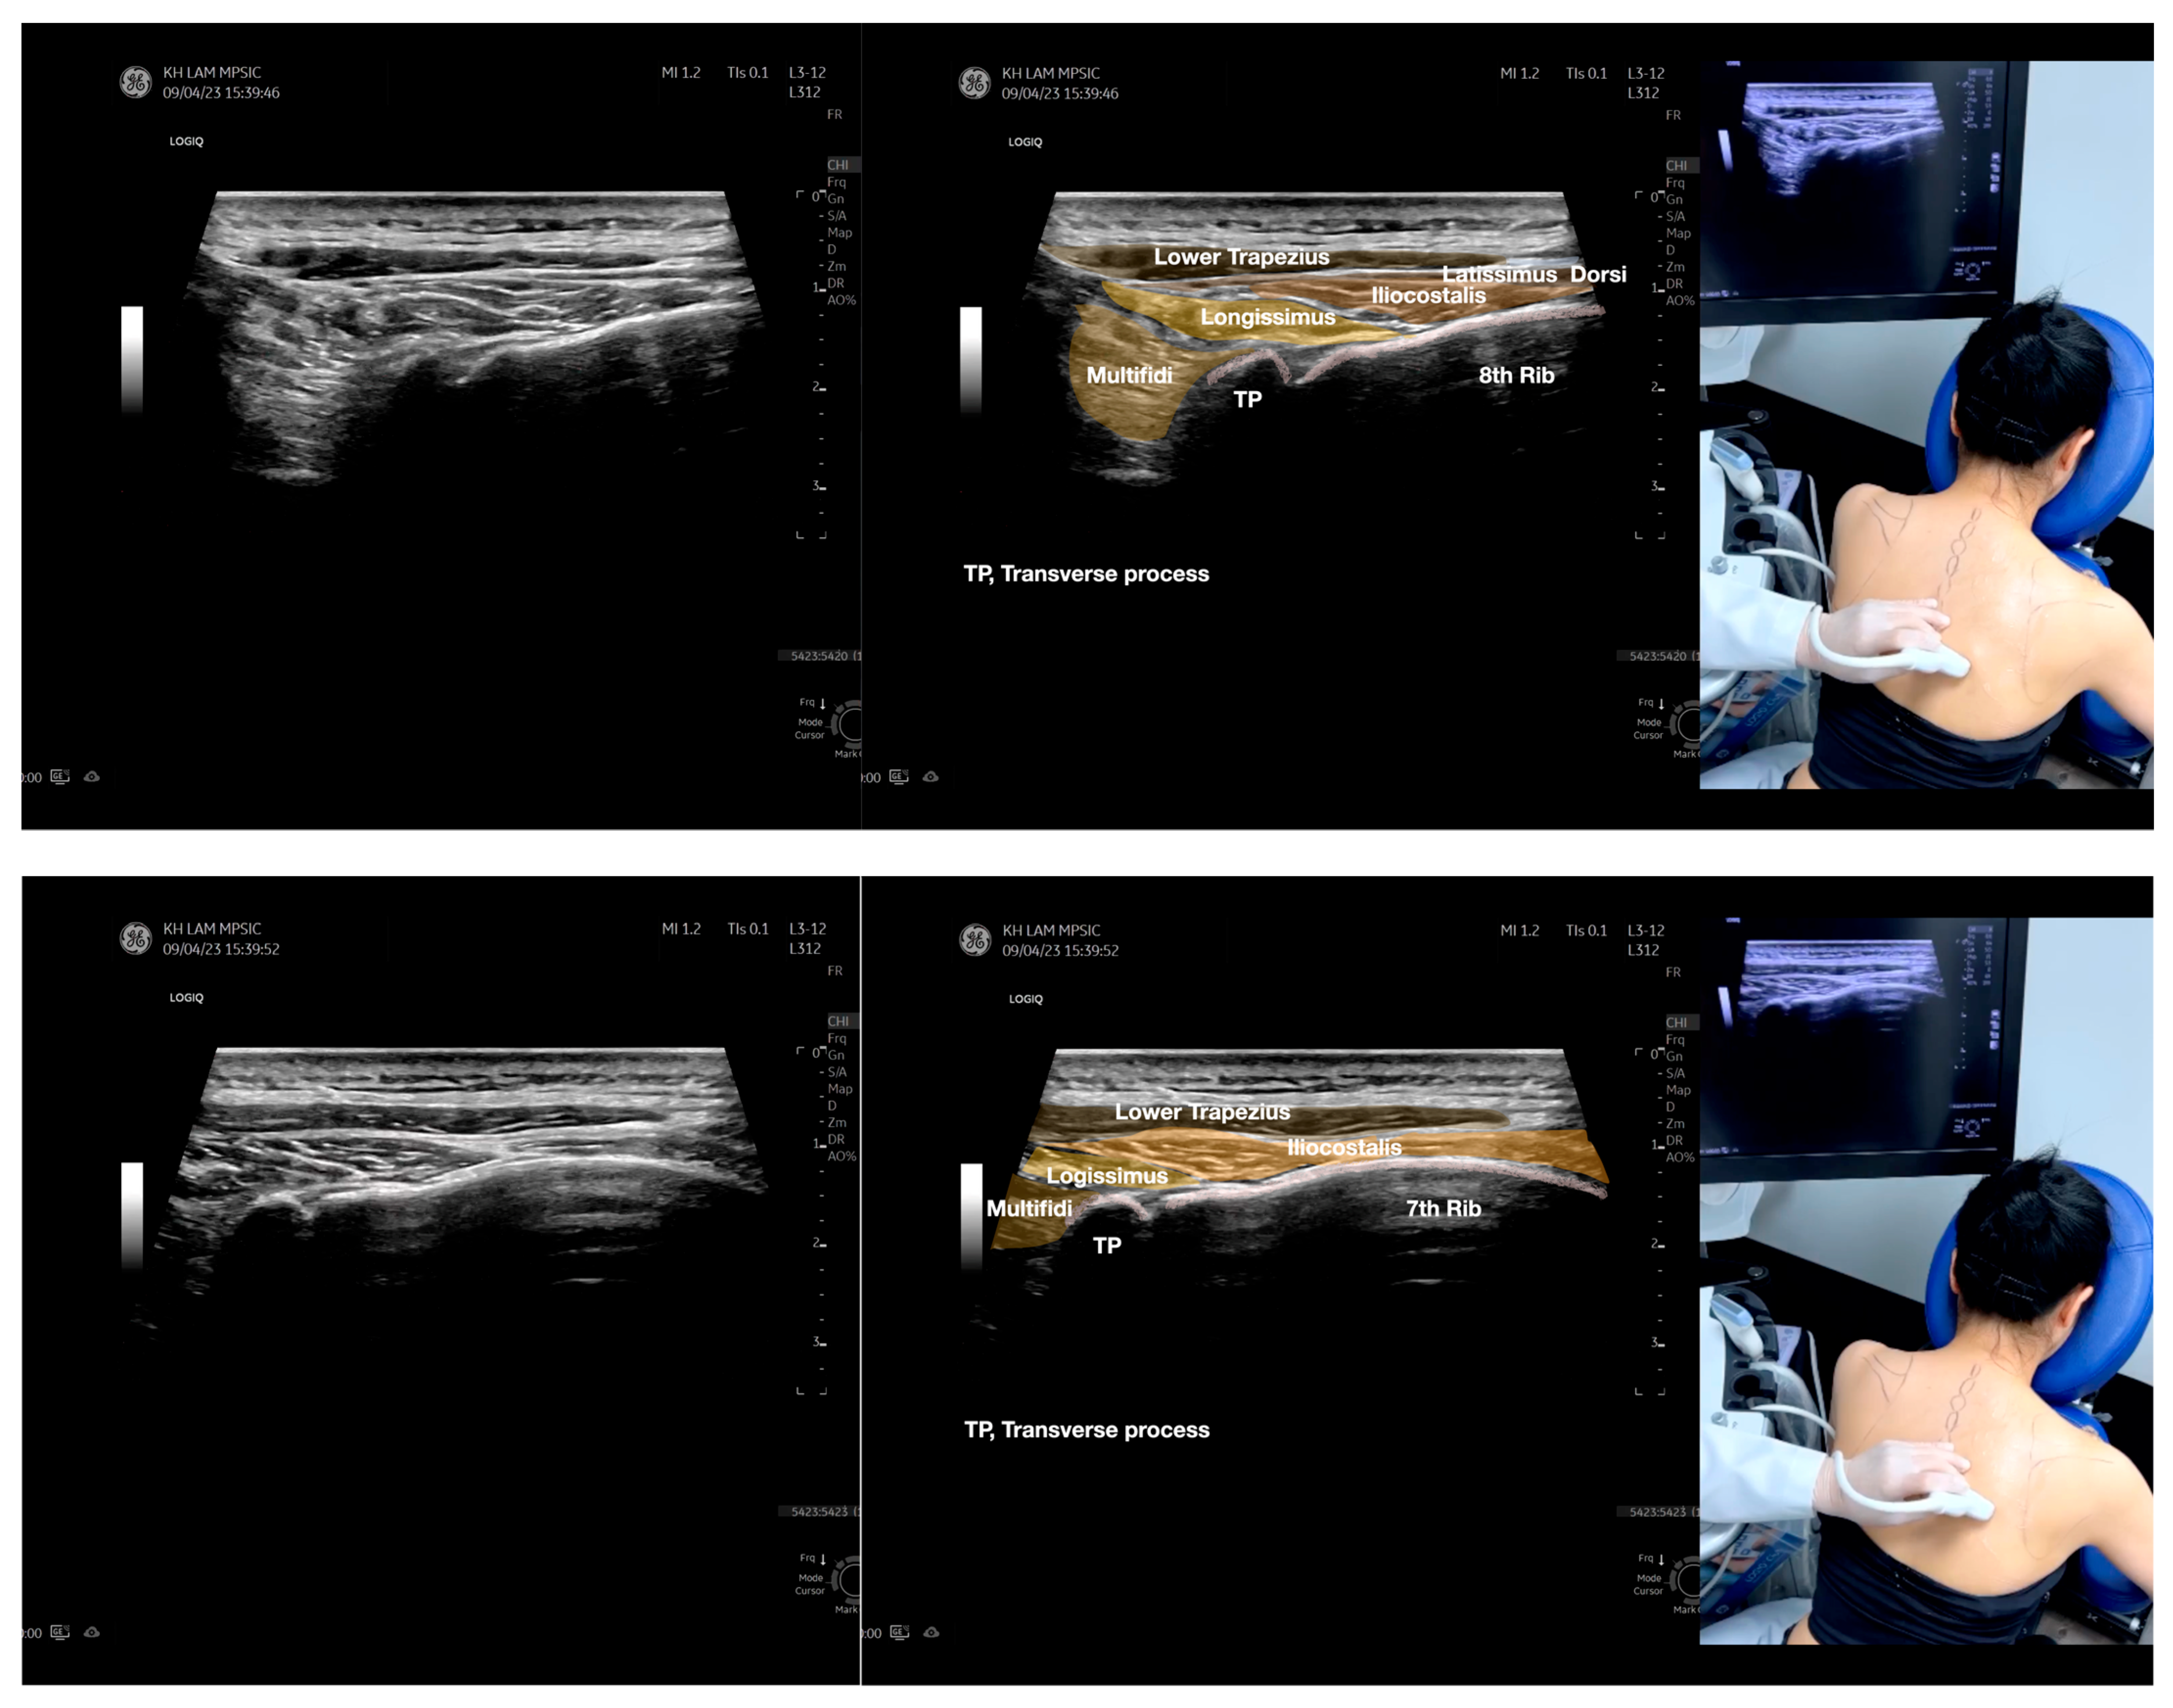

Figure 5.

Sonoanatomy of scanning the infraspinatus fascia in the sagittal plane from the rhomboid minor laterally, then back to the rhomboid major. The step-by-step scanning techniques of the structures illustrated in this figure have been shown in Video S9. Available online: https://www.dropbox.com/s/gu9hhrdq9erin6n/Figure%205.docx?dl=0 (accessed on 1 January 2023).